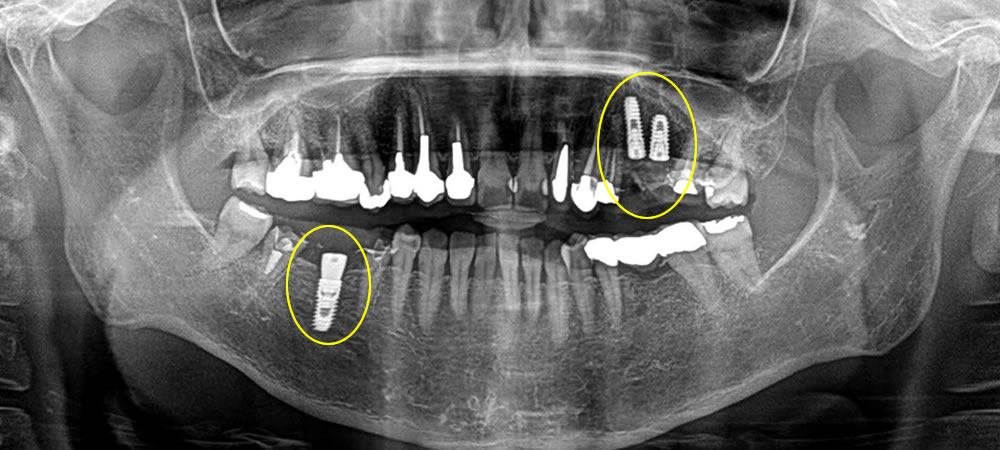

まずブリッジを除去し、残す事のできない歯を抜き、元々歯のない部位と歯を抜いた部位にインプラント治療を行いました。歯を抜き、即時でインプラントを入れる部位には埋入と同時に骨を作る処置(骨造成)を行い、特殊な縫合で傷口を閉鎖し、歯茎の形態も同時に調整していきました。

次に右下のブリッジの入っている部位もインプラントに変えていきたいとの希望により、ブリッジを除去し歯の無い部位にインプラントを埋入しました。

元々歯の無い部位に行う埋入は7ミリ程度の切開にて行いました。低侵襲で行う事により、痛み腫れを最小限に抑えて施術を行う事ができました。